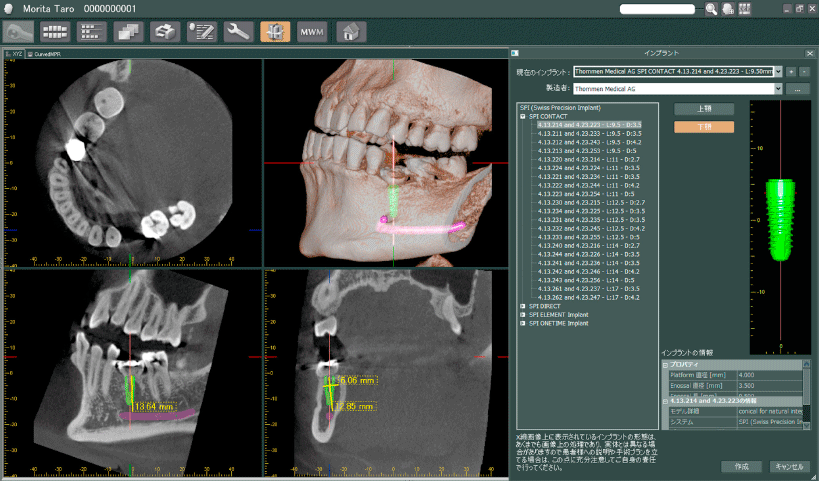

インプラント治療とCT

インプラント治療では、術前の骨の状態(質や厚み、高さ、形態など)を正確に判断ができるので、切開や剥離をしない手術など に対して、すぐに判断が可能です。歯科用CTでの撮影画像をもとに、的確な治療計画を立てることは、安心・安全な治療への第一歩です。